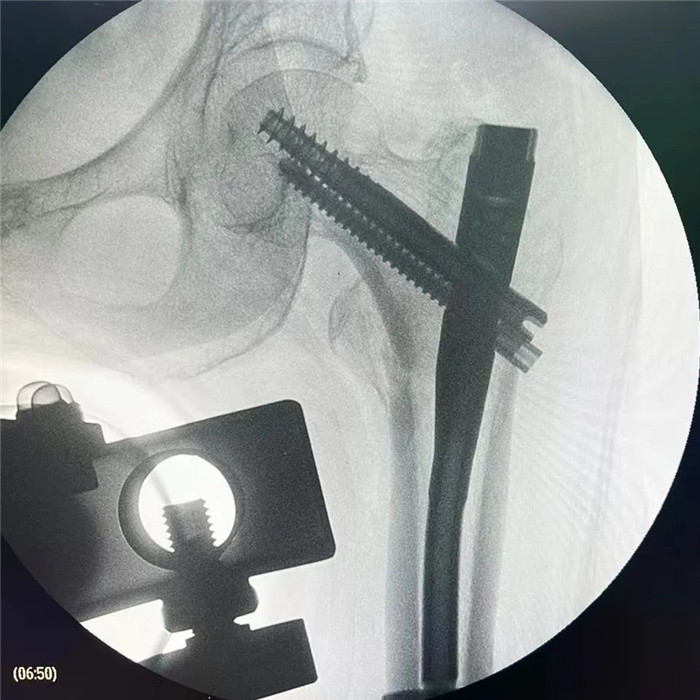

在手術(shù)團(tuán)隊(duì)及患者家屬的大力支持下,羅軍主任團(tuán)隊(duì)為洪阿婆實(shí)施了閉合復(fù)位INTERTAN內(nèi)固定術(shù)。雖然手術(shù)風(fēng)險(xiǎn)較大,但憑借精湛的技術(shù)及豐富的臨床經(jīng)驗(yàn),手術(shù)十分成功而且僅僅用了1個(gè)小時(shí),術(shù)中出血不多,術(shù)后患者恢復(fù)得很好,第二天就可以在起床活動(dòng),極大的提高了患者的生活質(zhì)量,避免了長(zhǎng)期臥床造成的并發(fā)癥。